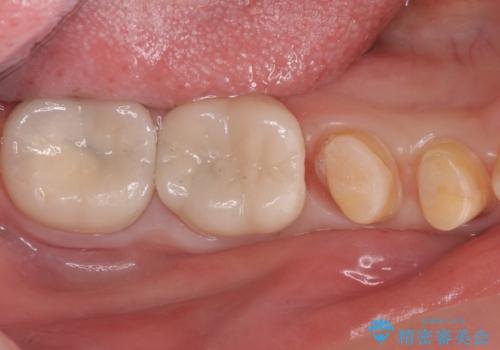

樹脂で継ぎ接ぎになった歯 セラミッククラウンでの治療

- 樹脂の材料の着色が気になるとのことで来院されました。

継ぎ接ぎになっている部分が多かったためクラウンでの治療となりました。

- 右下45:仮歯+ジルコニアクラウン/11,000円+110,000円費用は治療当時の料金となります

樹脂の材料と歯の境界部分は虫歯・着色の好発部位となります。

度重なる治療で継ぎ接ぎになってしまった場合はクラウンで歯を覆った方が虫歯・着色のリスクを減らすことができます。